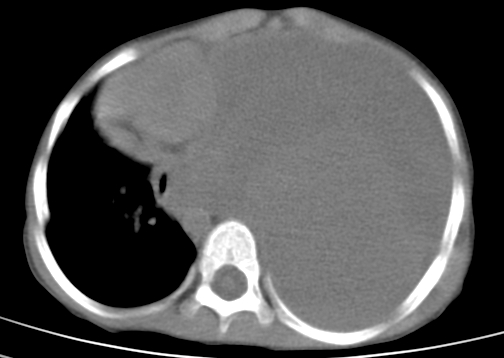

患儿 女 4岁,发热 咳嗽 胸透 考虑:左侧脓胸

左侧胸廓内见大量密实阴影,肺尖部尚有少量肺组织影,纵膈明显受压移位,肋骨未见明显受侵征象,虽然病人年龄较小,但如此大量的“积液”,还是要警惕,不同意一般感染,可结合穿刺脱落细胞学检查。

左侧大量胸腔积液。原因?

左侧张力性大量胸腔积液压迫性肺不张、感染;建议治疗后复查。